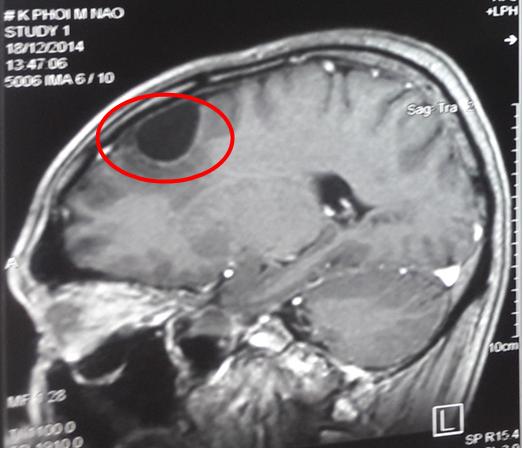

-       Chụp cộng hưởng từ sọ não: tổn thương dạng dịch hóa vùng trán đỉnh phải kích thước 25x15mm.

Hình 4: Hình ảnh chụp cộng hưởng từ sọ não sau xạ phẫu bằng dao gamma quay liều 18Gy, khối u không còn chỉ có tổn thương dạng dịch hóa vùng trán đỉnh phải (vòng tròn đỏ).

Nhận xét: Sau 6 tháng điều trị Tarceva kết hợp với điều trị xạ phẫu tổn thương di căn não bằng dao gamma quay, bệnh đáp ứng một phần, tổn thương di căn não biến mất chỉ còn ổ dịch hóa kích thước nhỏ.